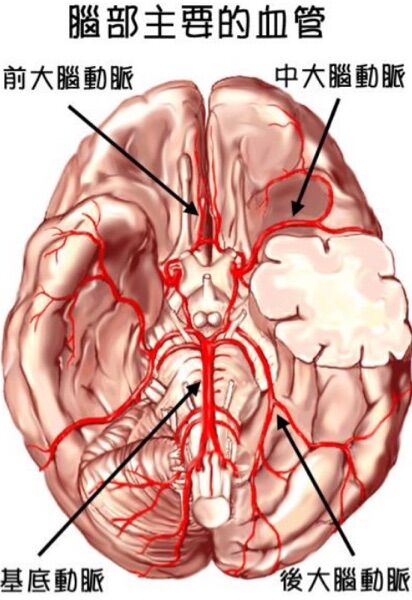

(B) 前大腦動脈梗塞型中風

(C) 中大腦動脈梗塞型中風

ACA、MCA、PCA的範圍如圖: